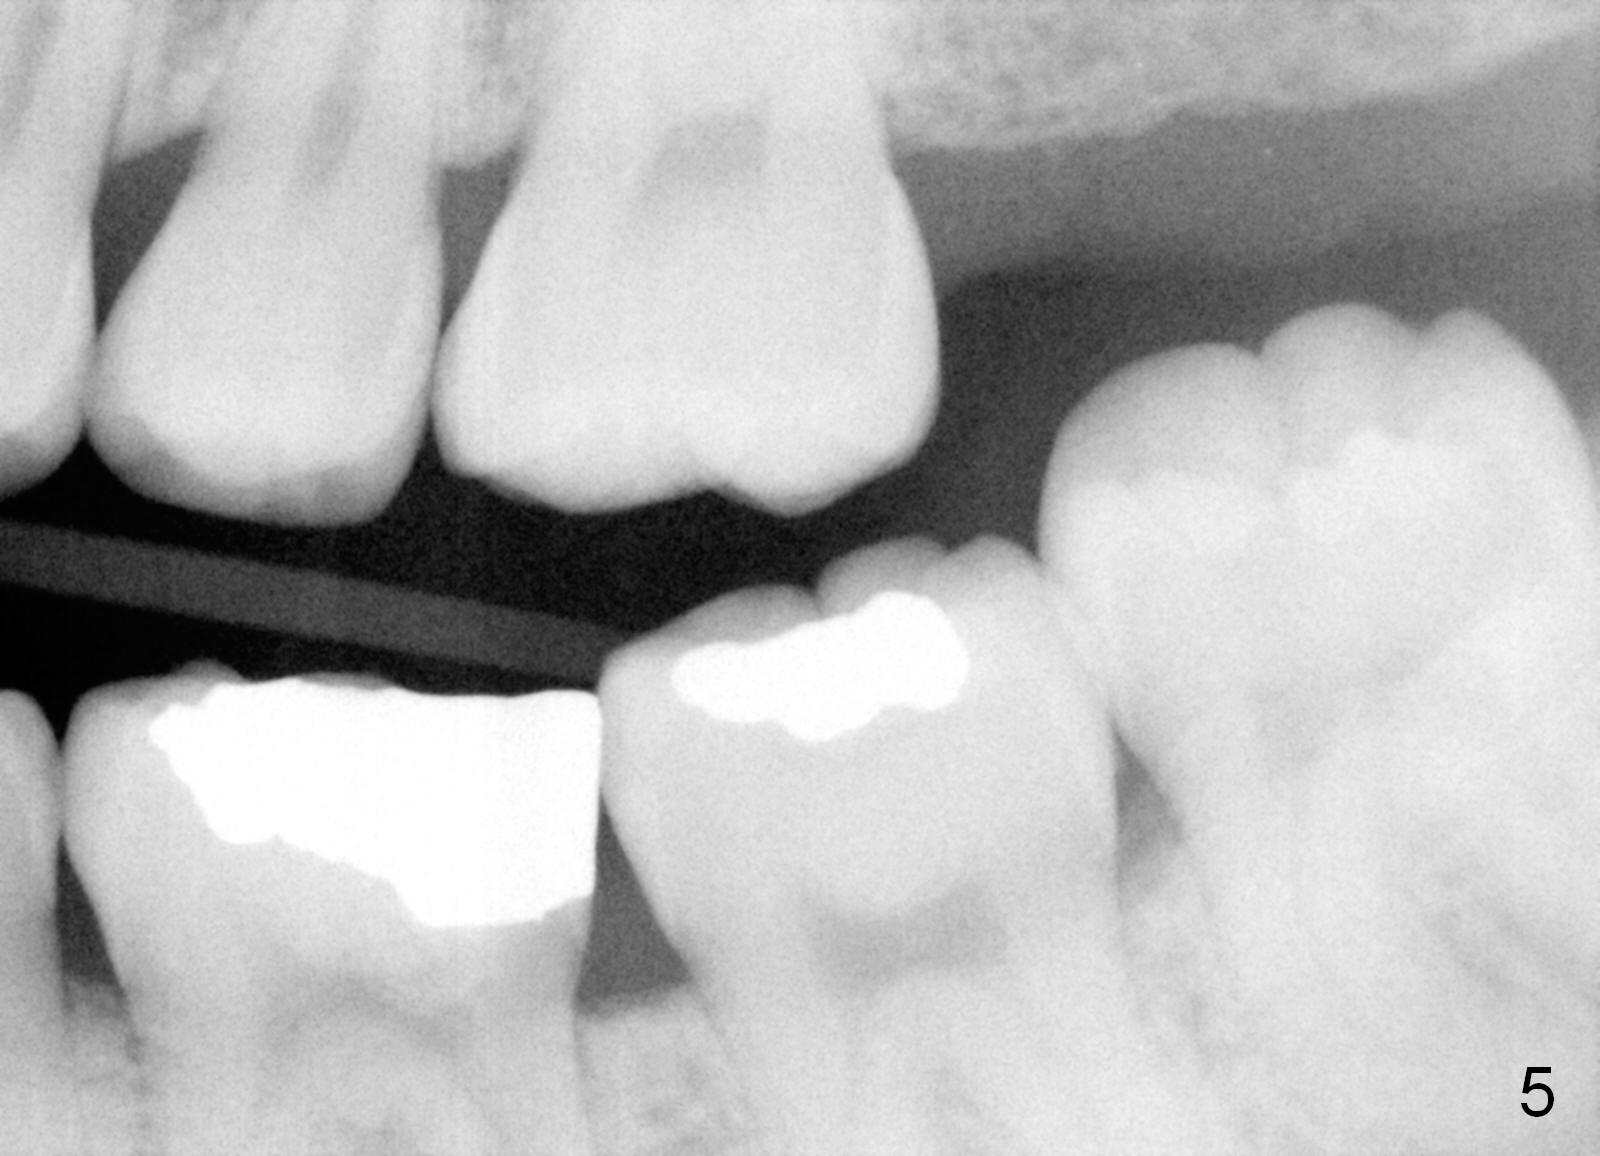

The panoramic X-ray (Fig.1) was taken on 12/12/2011 when the teeth #15 and 16 were extracted. The teeth #1 and 2 were removed half a year later. Bitewings (Fig.2-5), PAs (Fig.6,7) and upper occlusal mirror photo were taken on 02/11/2015. Pay attention to Fig.2.